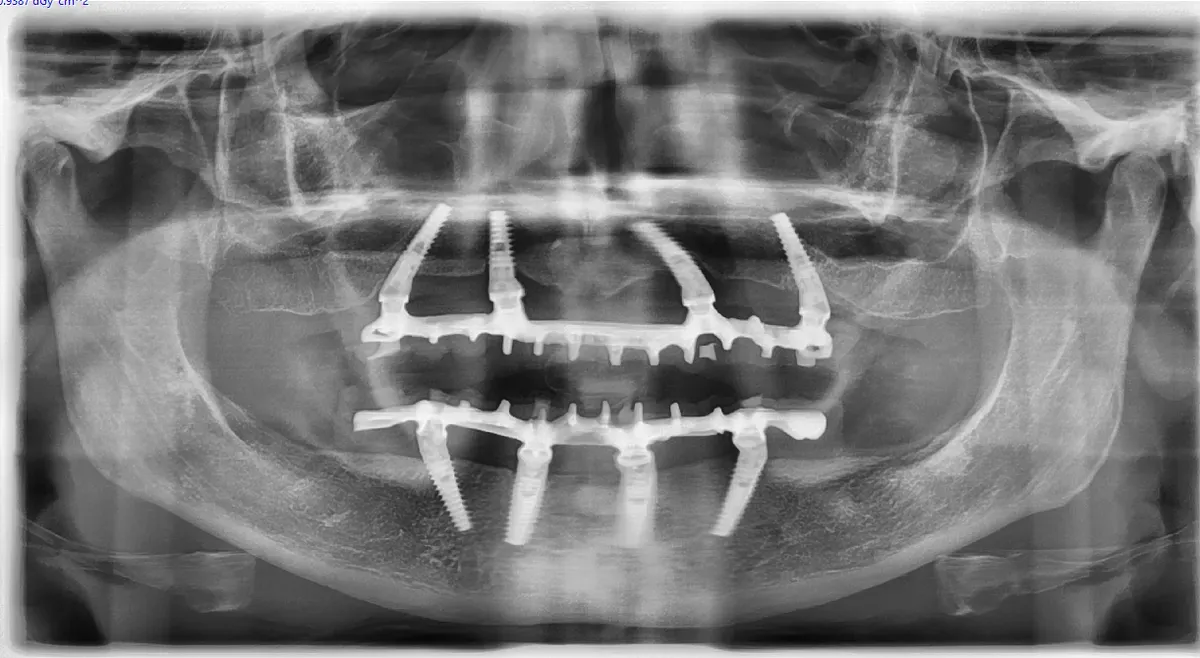

Le immagini radiografiche che seguono testimoniano alcune delle tante soluzioni tecniche che ho utilizzato per le arcate a carico immediato nel corso della mia carriera. Ogni caso presenta sfide diverse e richiede un approccio personalizzato.

Personalmente, amo scegliere il numero e le misure degli impianti in base alle caratteristiche anatomiche del singolo paziente, piuttosto che affidarmi a protocolli troppo rigidi e standardizzati. Sempre nell’ottica della rigenerazione su misura, ritengo che ogni caso debba essere studiato individualmente per ottimizzare il risultato finale.